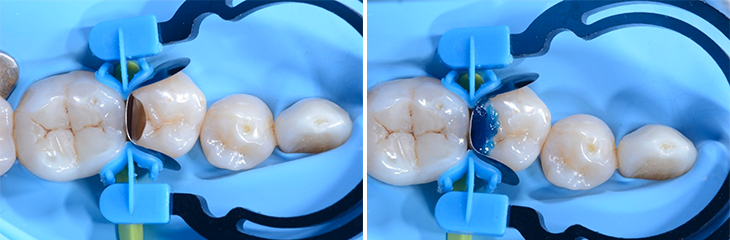

4. Prémolaire 45 dotée d’une matrice sectorielle LumiContrast et myWedge

Le positionnement correct de la matrice sectorielle LumiContrast est essentiel pour le succès de la restauration des parois proximales ; l’image de gauche (x) montre le positionnement incorrect de la bande matricielle ; pour une restauration optimale du point de contact, la bande matricielle doit dépasser la paroi proximale comme montré sur l’image à droite (v).